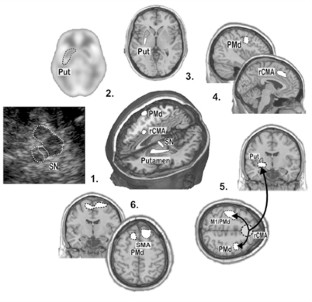

Abb. 1

Abb. 2